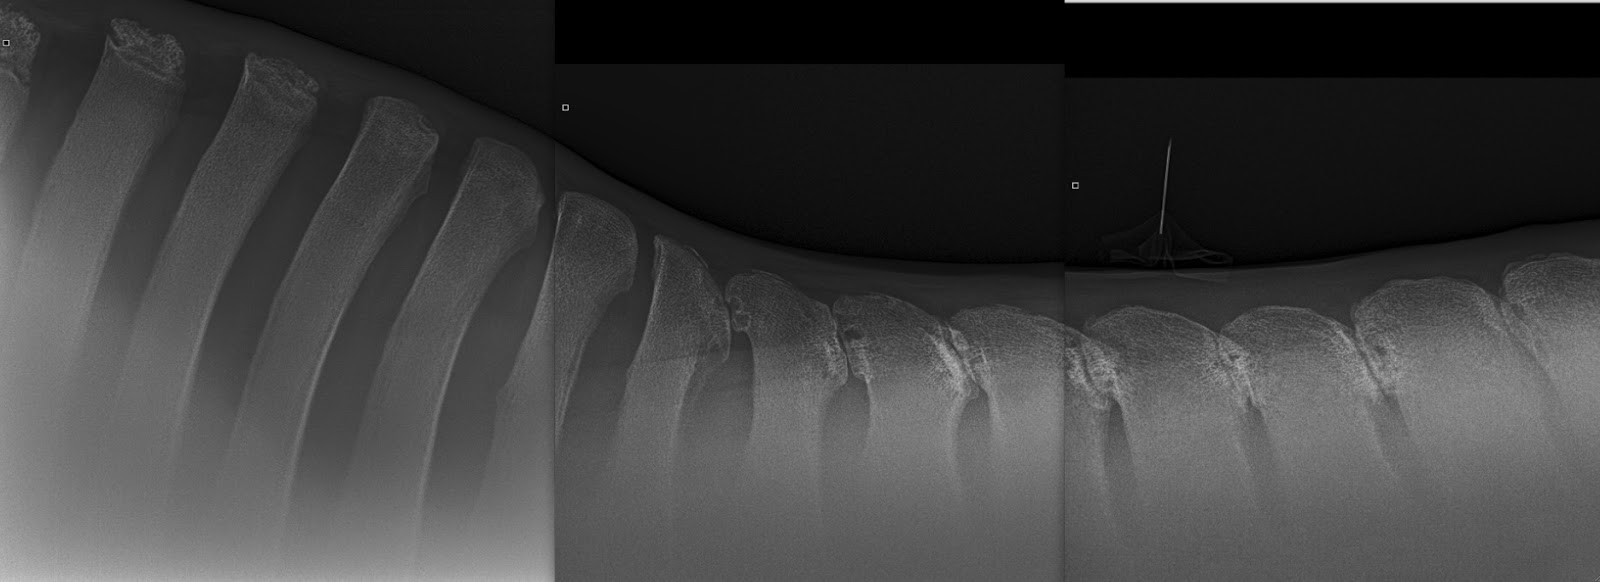

Quir schreef:Dat is geen kraakbeen. Dat zijn epifysair schijven, ofwel groei schijven. Kraakbeen zie je niet p de foto

Ik heb denk ik nog wel foto's van normale schoft. Zal even kijken

Edit: van Google.

http://3.bp.blogspot.com/-O2nHSbsp1pA/U ... gether.jpg